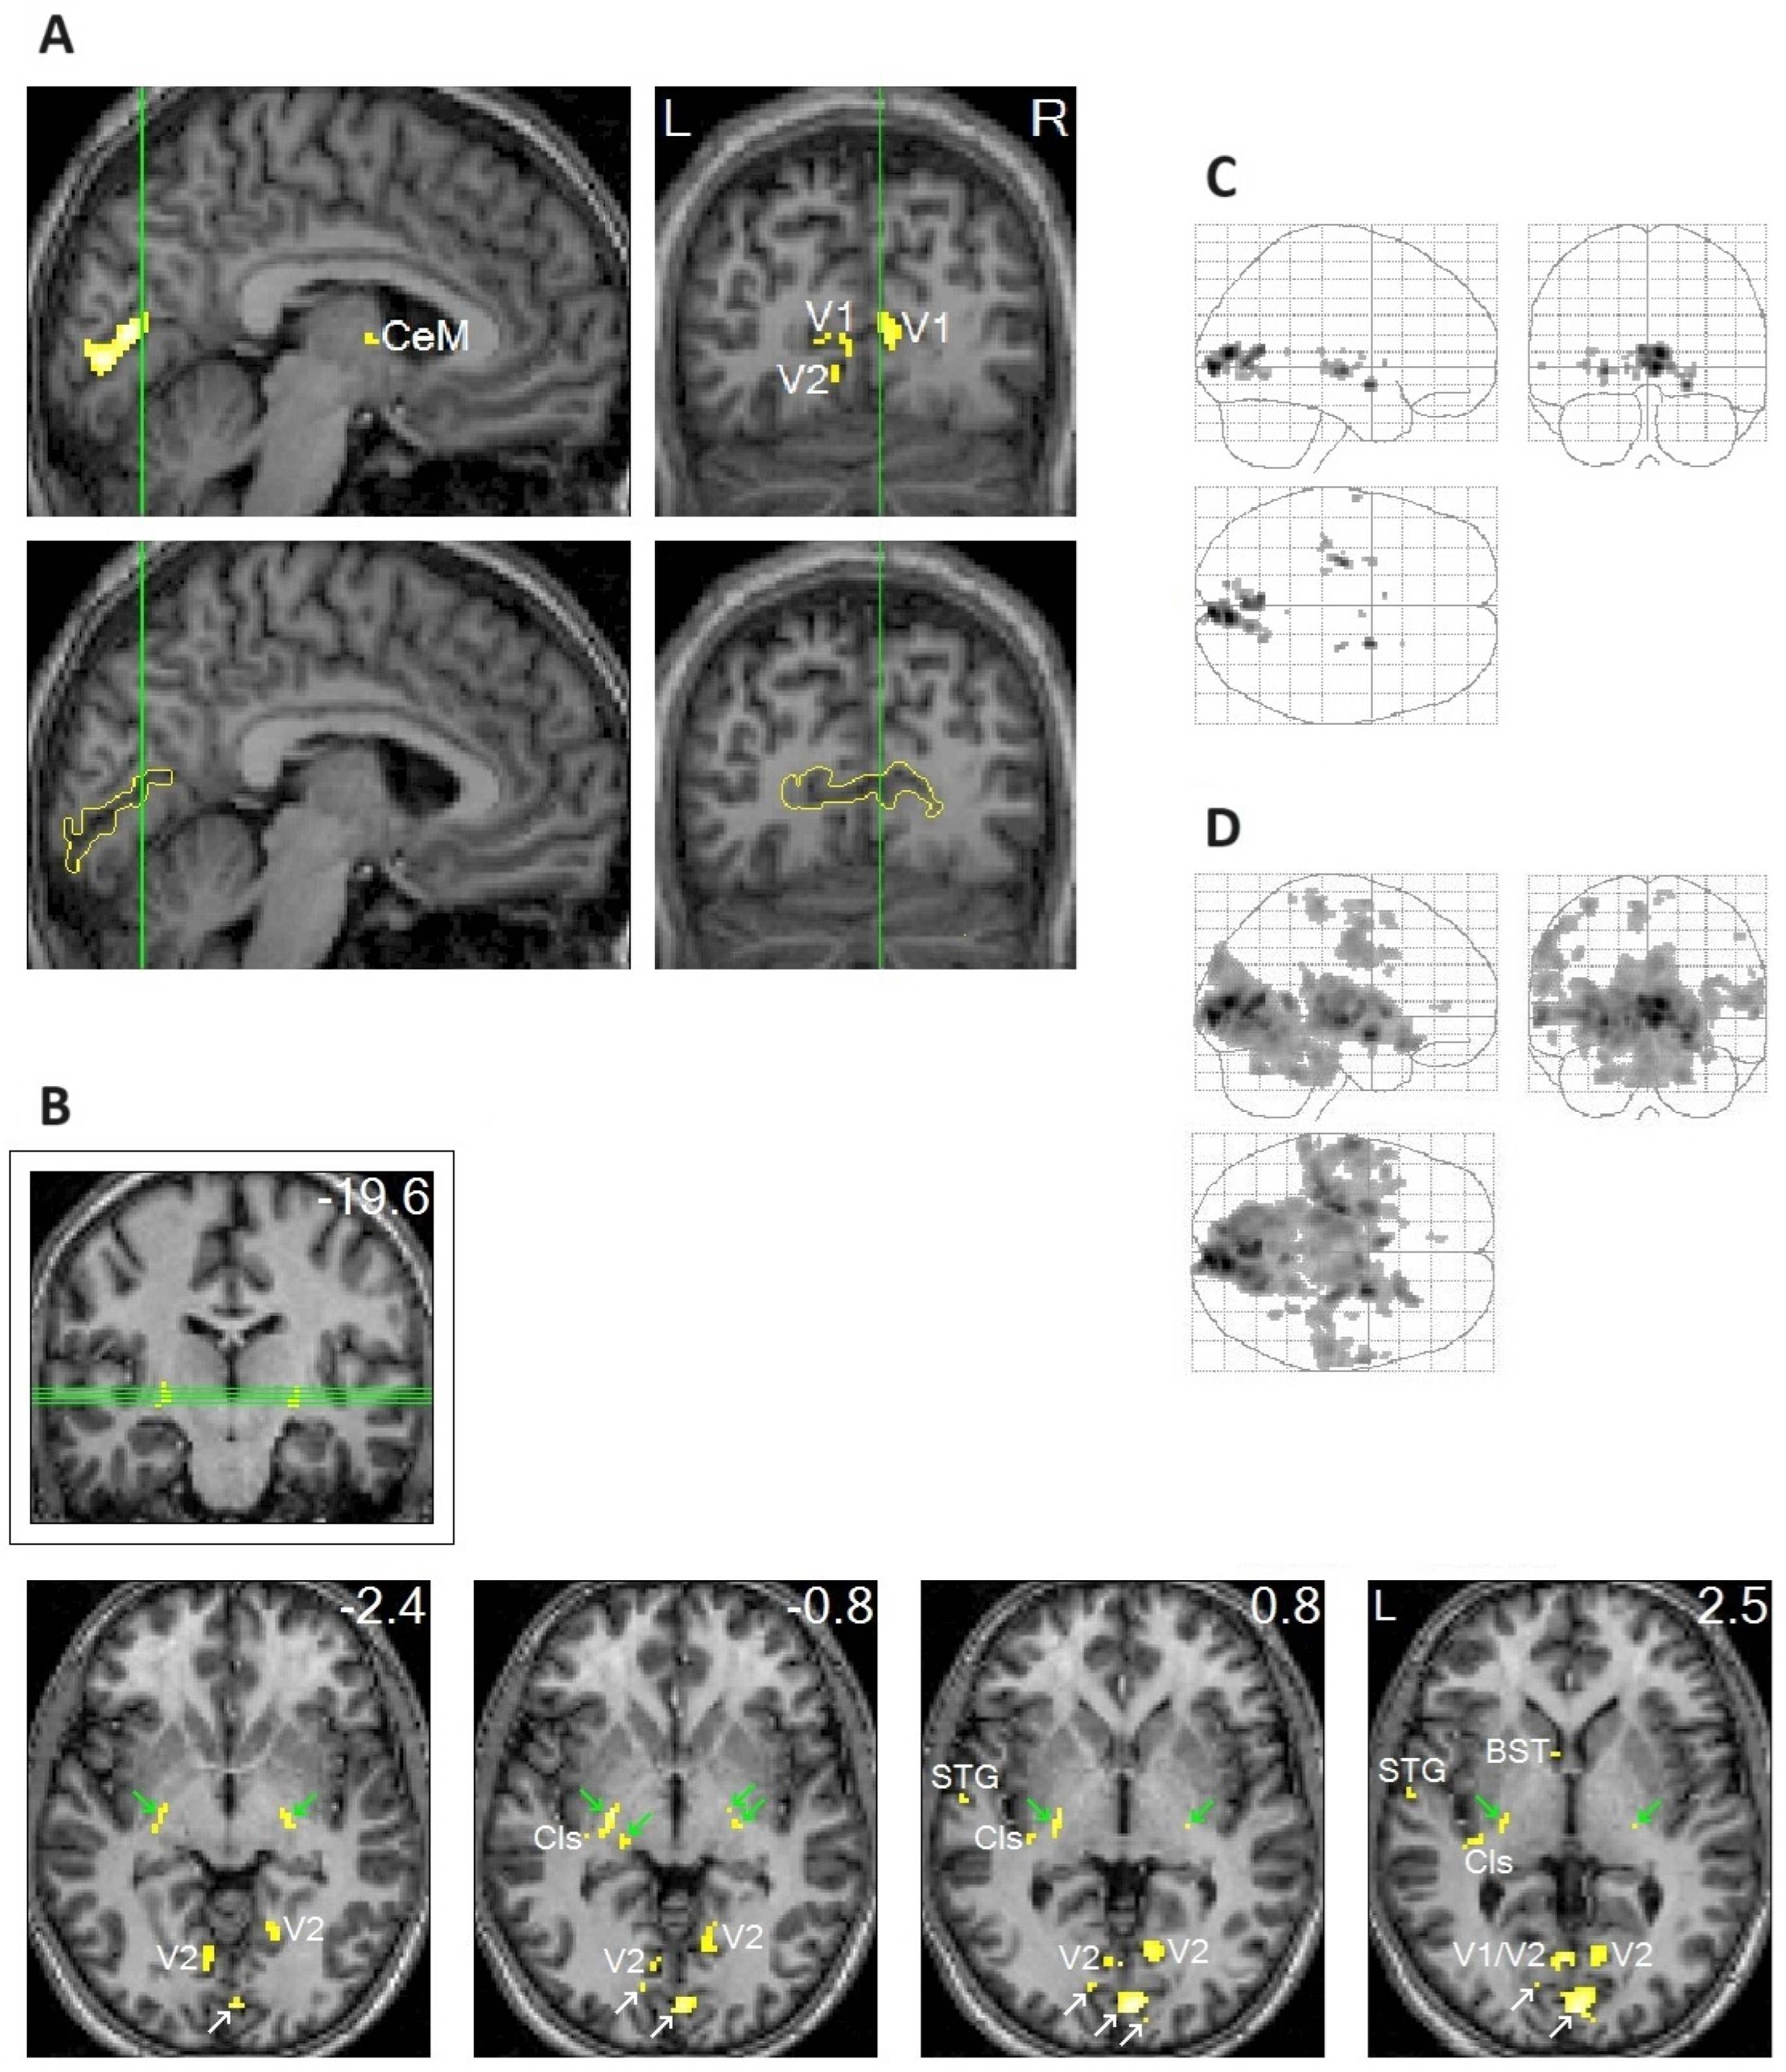

- Hong, C.C.-H.; Harris, J.C.; Pearlson, G.D.; Kim, J.-S.; Calhoun, V.D.; Fallon, J.H.; Golay, X.; Gillen, J.S.; Simmonds, D.J.; van Zijl, P.C.M. fMRI evidence for multisensory recruitment associated with rapid eye movements during sleep. Hum. Brain Mapp. 2009, 30, 1705–1722. [Google Scholar] [CrossRef]

- Hong, C.C.-H.; Fallon, J.H.; Friston, K.J. fMRI evidence for default mode network deactivation associated with rapid eye movements in sleep. Brain Sci. 2021, 11, 1528. [Google Scholar] [CrossRef]